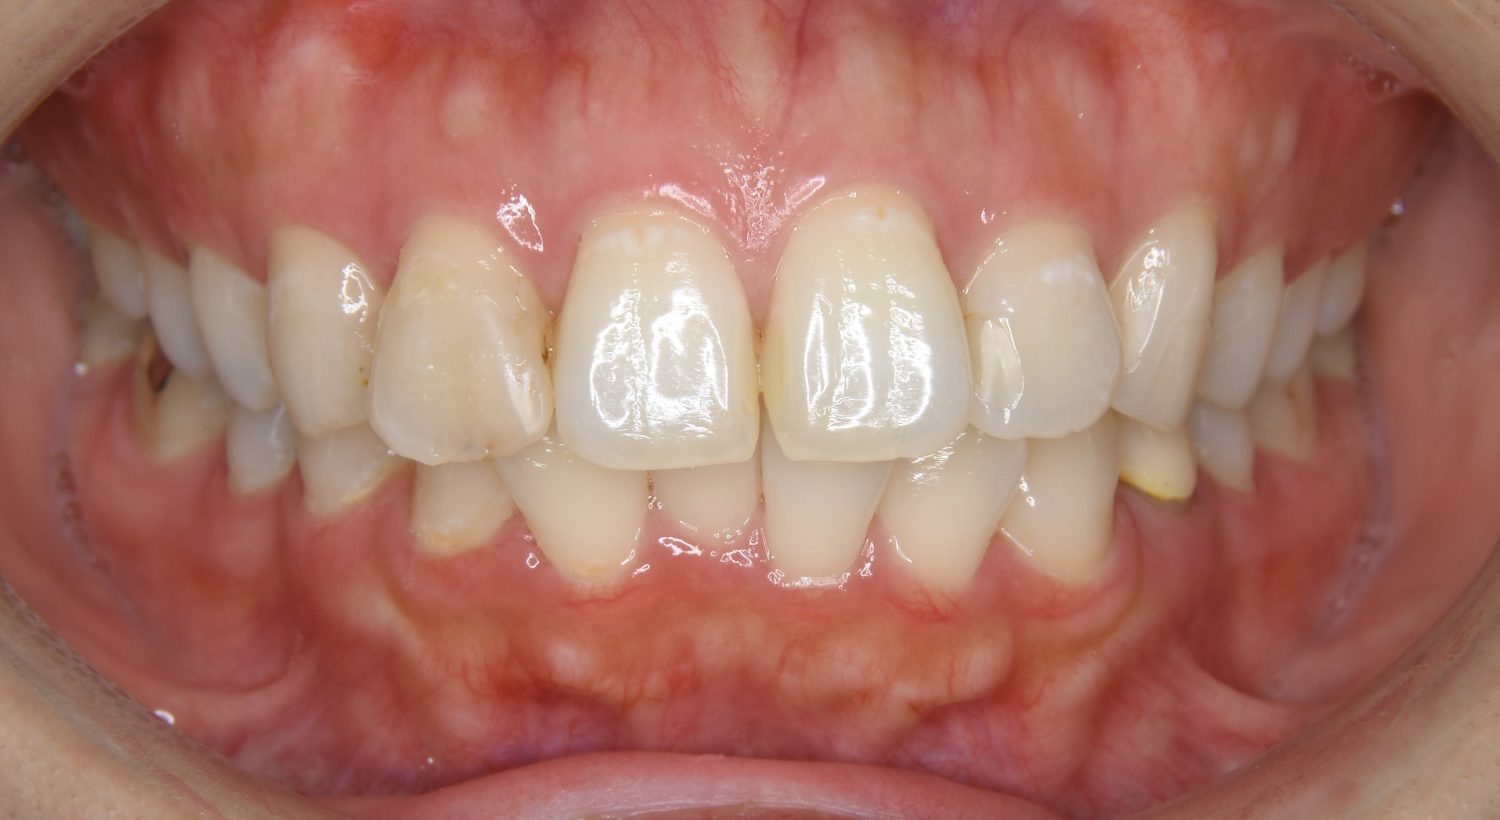

Before

上下の前歯が開いており前歯では全く噛めていない状態でした。臼歯の圧下を行うことで前歯でも咬合できるようになり機能面のみでなく審美面も著しく改善しました。